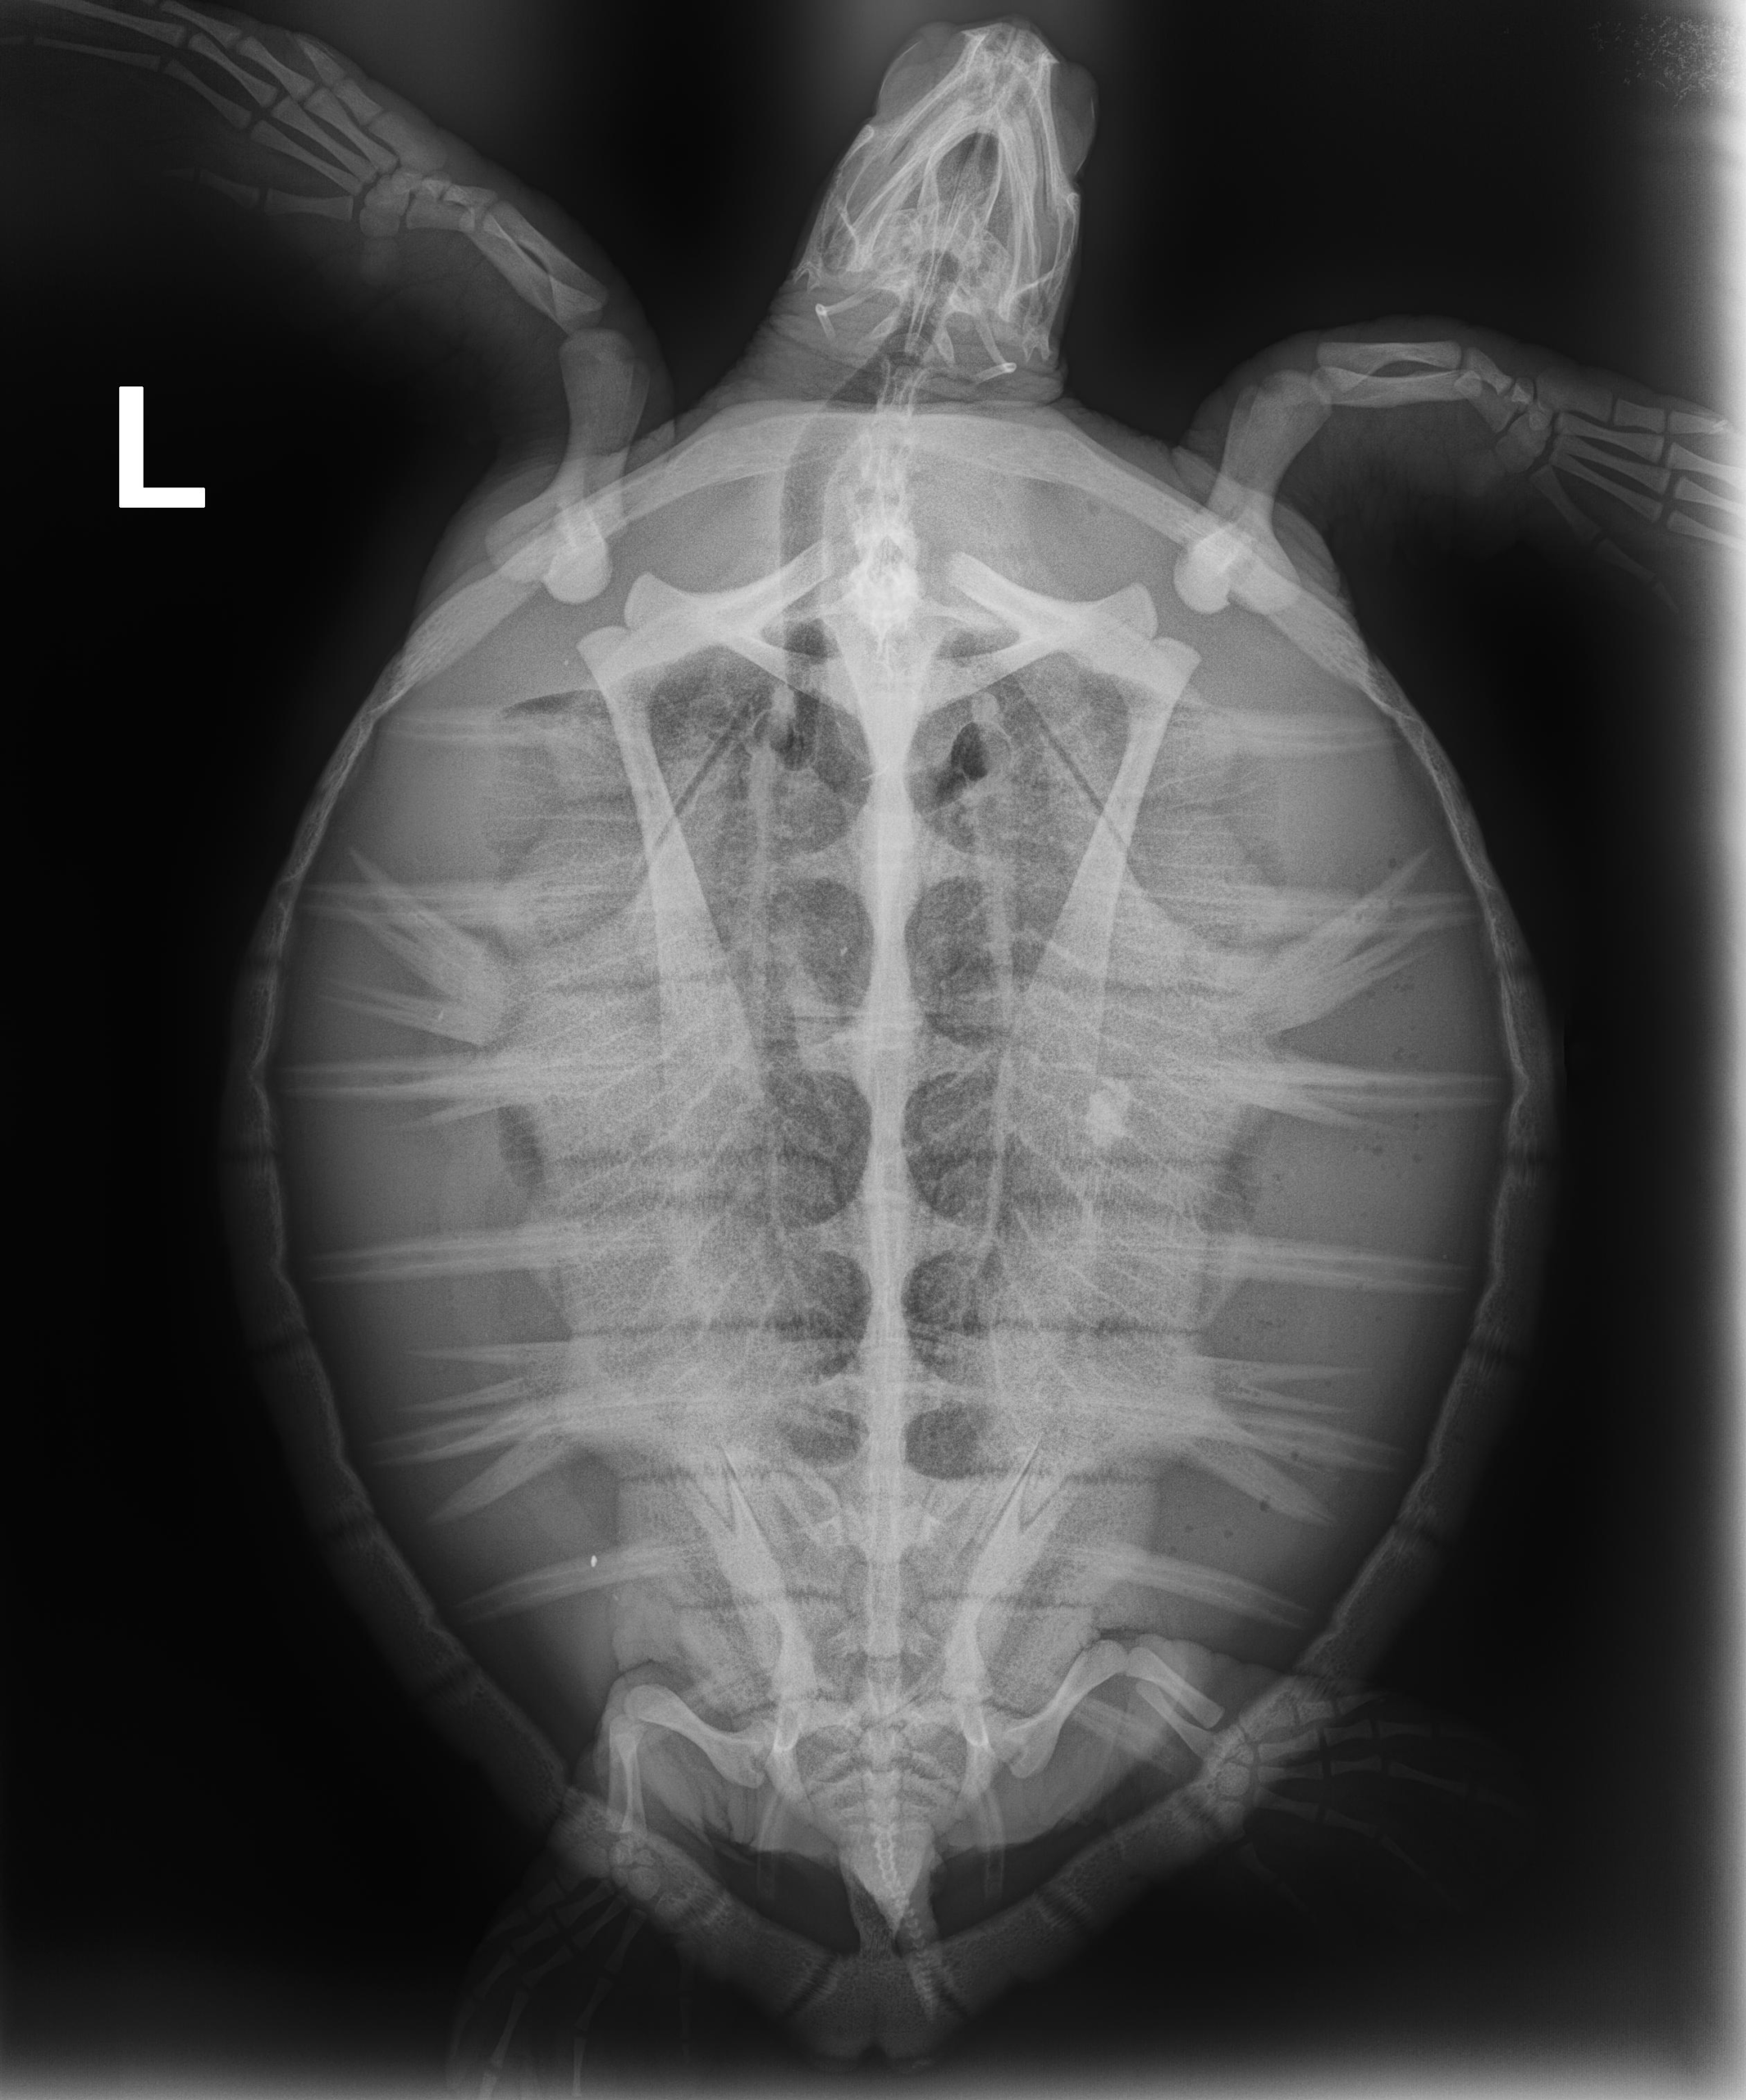

8.9 lbs. non-FP juvenile green

Minor hook wound on left front flipper and minor abrasions on carapace and plastron